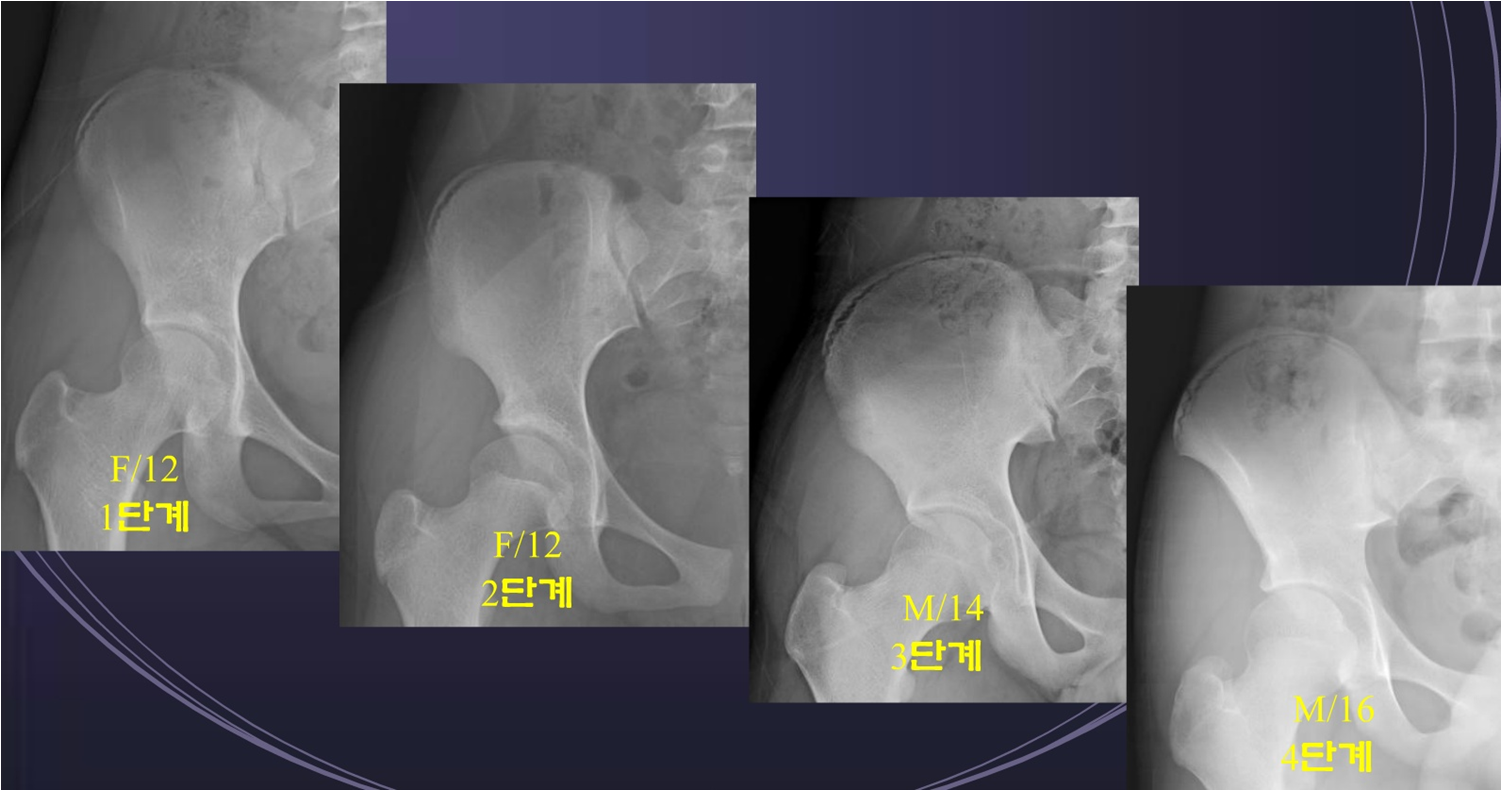

보조기 착용 중지 시기로는 유방, 성기 및 치모의 발달하면 중지하고, Risser Grade 4단계 이상일 때, 착용시간을 점차 줄이며 중지 하게 된다.

Risser Grade란 Pelvis의 iliac crest부분이 골단이 자라난 정도의 단계로 남은 성정과 곡선의 진행 위험 평가를 결정하는 도구로 쓰인다.

Risser Grade가 낮을 수록 진행이 빠르다.